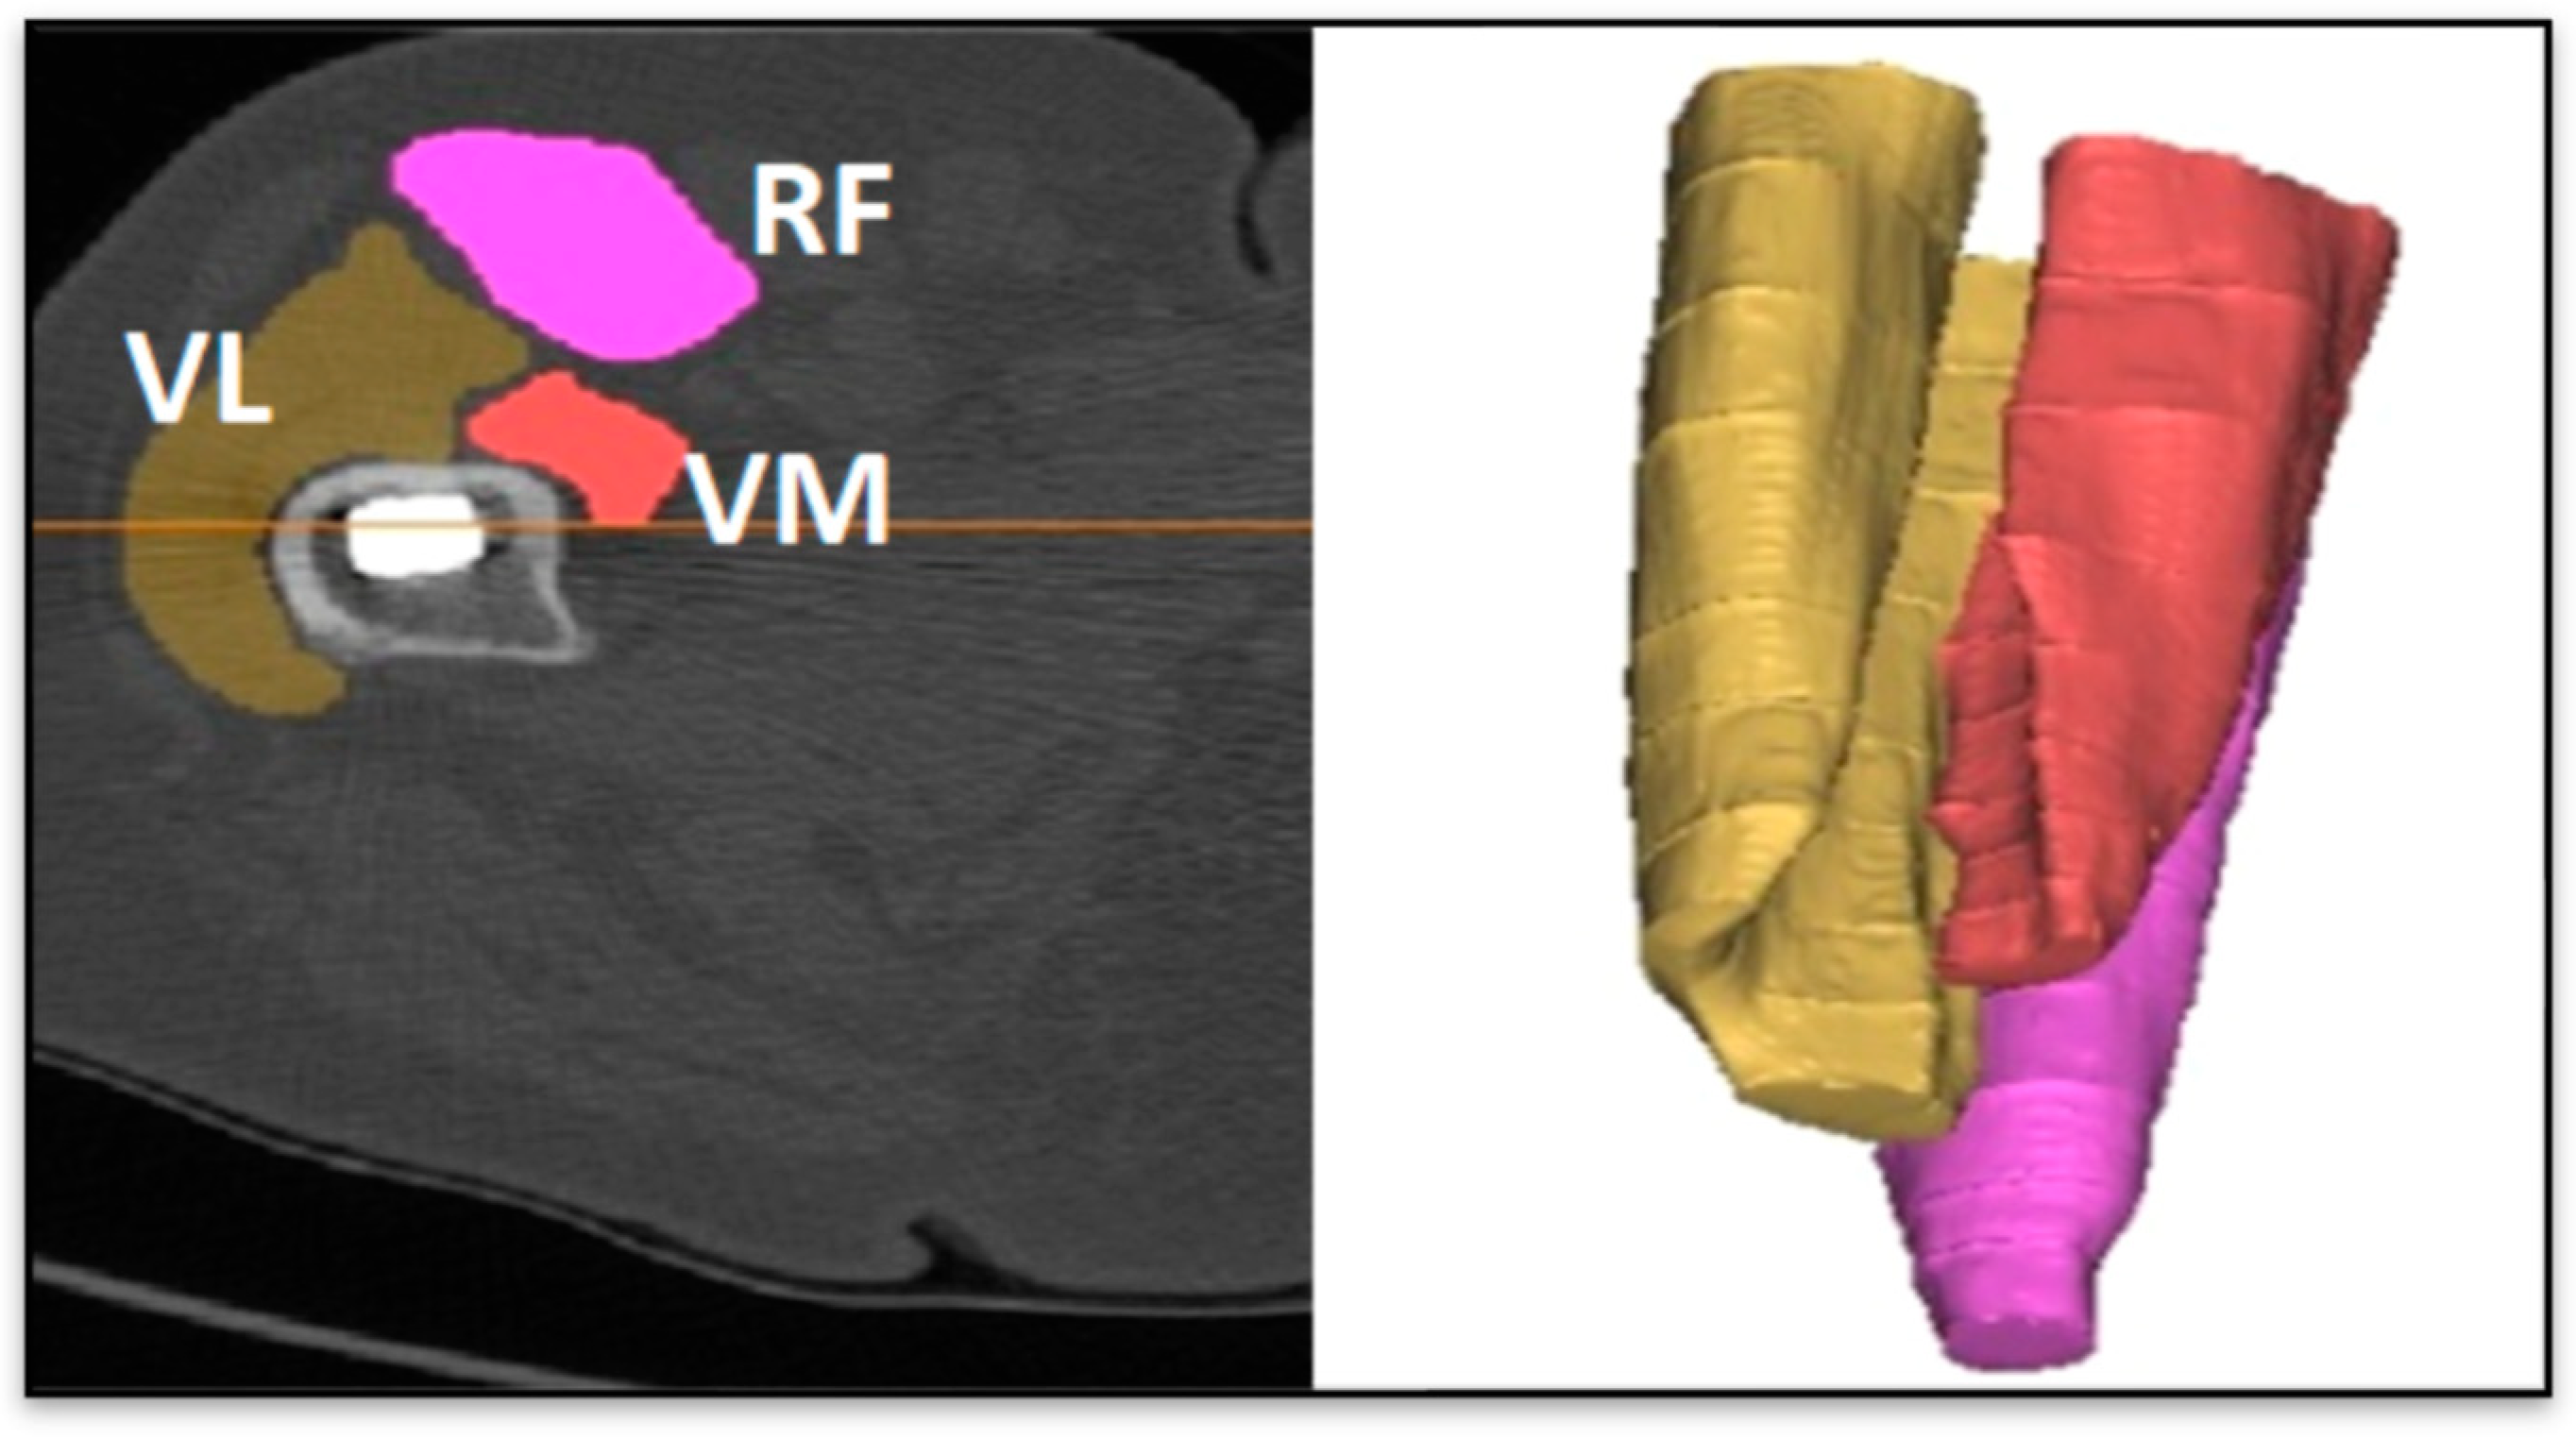

| VM Operated HU | Healthy leg BMD | Start Healthy VL |

| VM Healthy HU | RFe Operated HU | Stop Healthy VL |

| Stop Healthy RFe | RFe Healthy Dev. Std. | Stop Operated VM |

| Start Healthy VL | VL Operated HU | Start Operated RFe |

| Start Operated VL | VL Healthy HU | Stop Operated RFe |

| VM Operated HU | Start Operated VL | |

| Start Healthy VM | Stop Operated VL | |